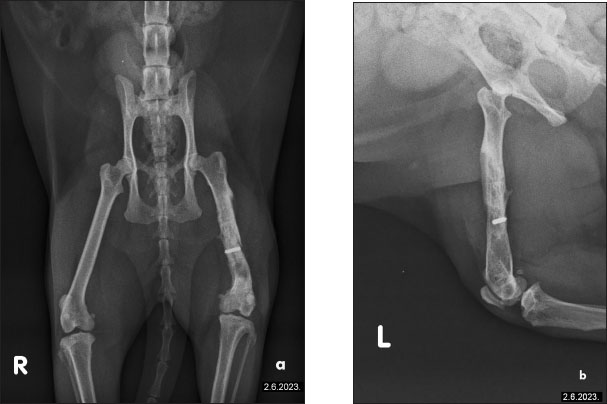

The cat had undergone orthopedic surgery 4 years ago, during which a plate was placed due to a femoral fracture (Fig. 2). Despite the surgery, the patient continued to show signs of discomfort, necessitating further diagnostics and therapy. During the examination at the radiology clinic, the cat showed signs of lameness and pain. The clinical examination revealed muscle atrophy of the left leg and pain on extension and flexion. Radiographic imaging of the pelvis and left femur revealed changes associated with the implant. Removal of the implant was recommended and subsequently performed. Figure 3 shows the radiographs of the cat’s left femur post-plate removal, showing 1 screw remaining in situ. Increased transparency in the medullary cavity indicates the need for LT to enhance healing and promote tissue regeneration.

Fig. 2. The radiographs of a cat’s left femur show (a) a ventrodorsal and (b) a mediolateral view following fracture repair using a 6-hole plate. The fracture is not visible, indicating satisfactory healing. Bone transparency is observed in the medullary cavity of the femur, further enhancing visualization of the internal bone structure. The plate is properly aligned, with no signs of complications.